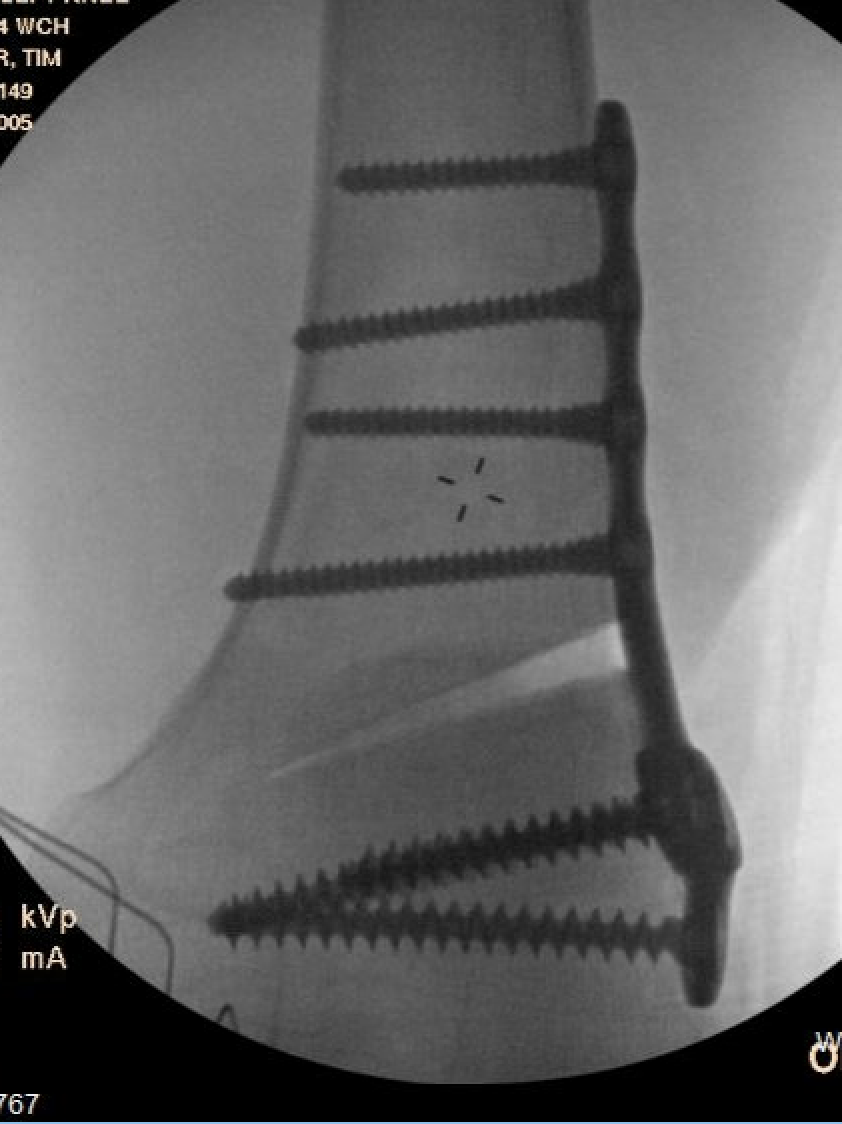

Medial Closing Wedge Osteotomy

Advantages

- lower risk of non union

- better for larger corrections

Disadvantage

- requires two osteotomy cuts

Distal Femoral Osteotomy MedialDFCO medial closing wedge

Technique

Osteotomy

- insert two K wires for desired wedge

- resect templated wedge

- stop 1 cm short of lateral cortex

- close femoral wedge